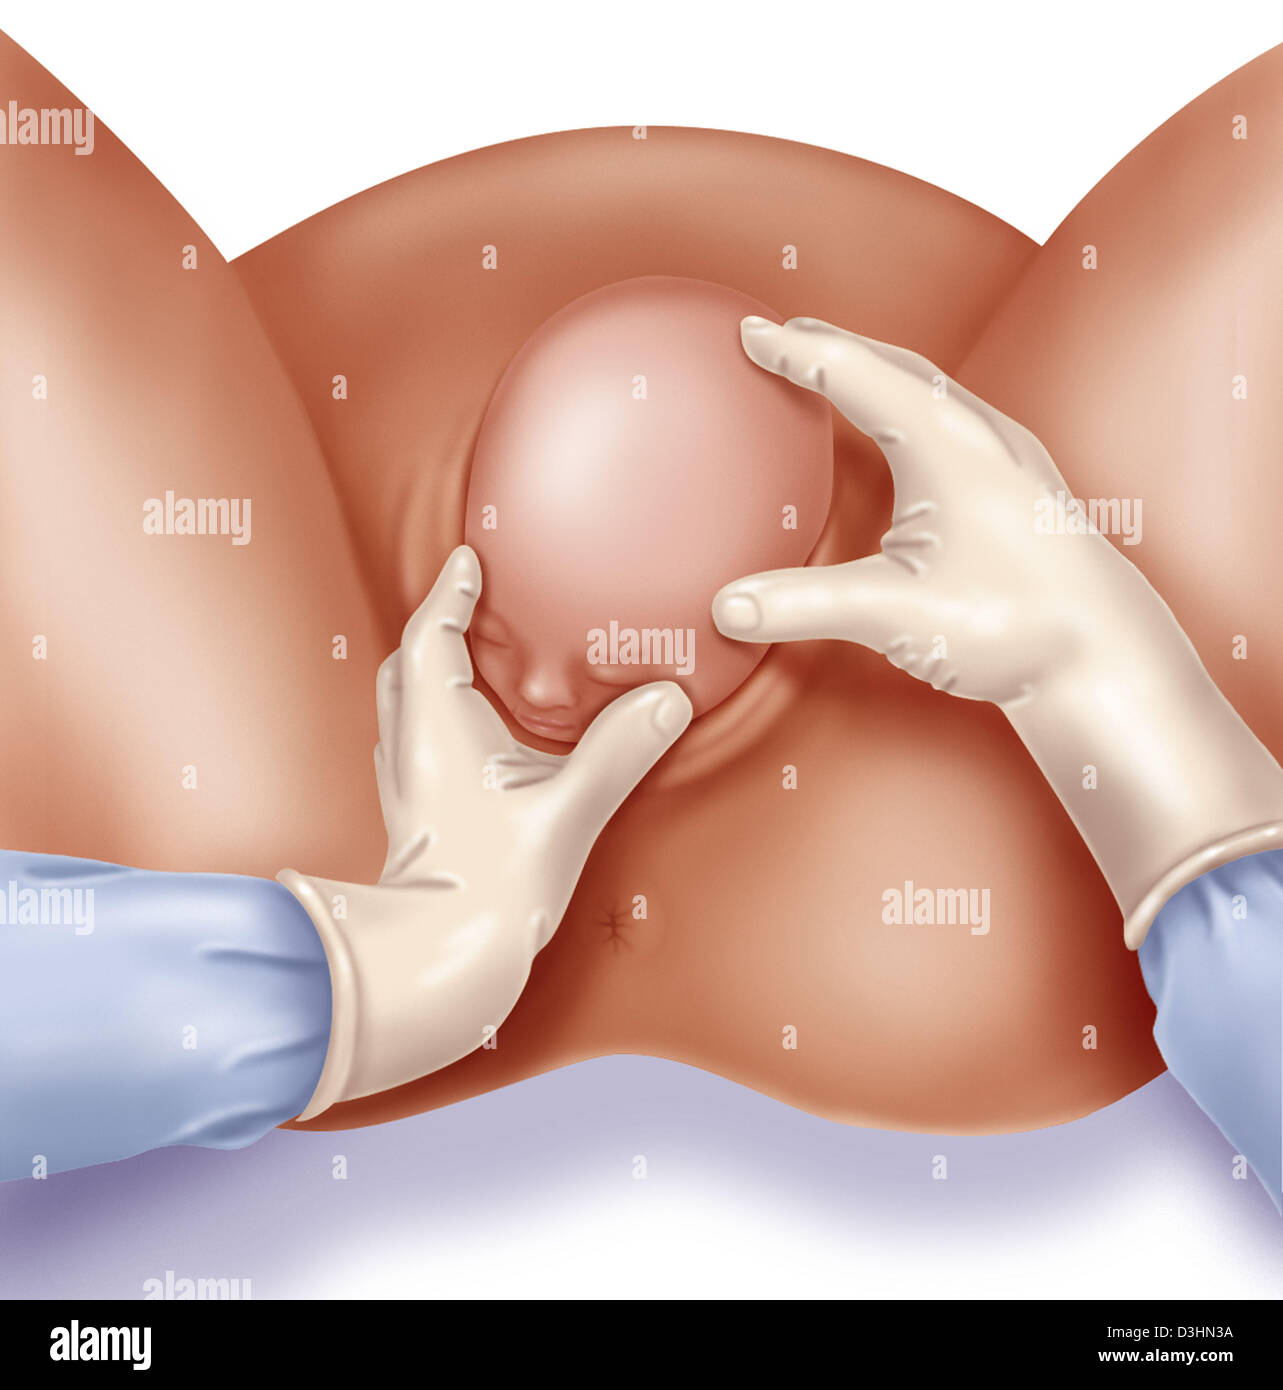

Childbirth, step 3: the baby's head is out. Stock Photohttps://www.alamy.com/image-license-details/?v=1https://www.alamy.com/childbirth-step-3-the-babys-head-is-out-image476926074.html

Childbirth, step 3: the baby's head is out. Stock Photohttps://www.alamy.com/image-license-details/?v=1https://www.alamy.com/childbirth-step-3-the-babys-head-is-out-image476926074.htmlRF2JKWT22–Childbirth, step 3: the baby's head is out.

Childbirth, stage 2: the baby's head is out. Stock Photohttps://www.alamy.com/image-license-details/?v=1https://www.alamy.com/childbirth-stage-2-the-babys-head-is-out-image476926096.html

Childbirth, stage 2: the baby's head is out. Stock Photohttps://www.alamy.com/image-license-details/?v=1https://www.alamy.com/childbirth-stage-2-the-babys-head-is-out-image476926096.htmlRF2JKWT2T–Childbirth, stage 2: the baby's head is out.